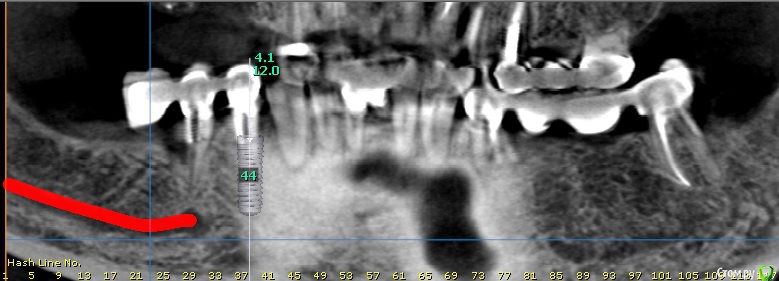

bilal Опубликовано 20 мая, 2019 Поделиться Опубликовано 20 мая, 2019 Подскажите, будут ли последствия, если я поставлю имплант в области 46. Смущает ответвление от основного канала, Ссылка на комментарий

Дмитрий М Опубликовано 21 мая, 2019 Поделиться Опубликовано 21 мая, 2019 как по мне так это костный рисунок такой покажите ответвление выколи глаз, не вижу Ссылка на комментарий

bilal Опубликовано 23 мая, 2019 Автор Поделиться Опубликовано 23 мая, 2019 (изменено) как по мне так это костный рисунок такой покажите ответвление выколи глаз, не вижу может и костный канал.импланты поставил, полет нормольный. Изменено 23 мая, 2019 пользователем bilal 2 Ссылка на комментарий